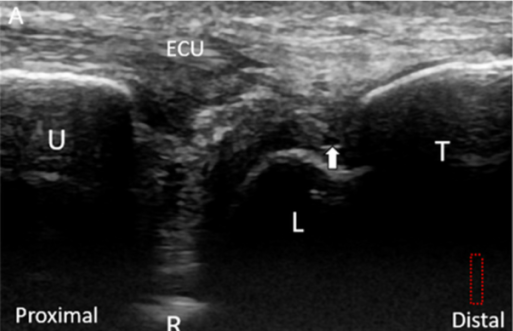

@ DOI: 10.3390/jcm8101540

관절 연골 외에도

반월 연골 유사체가 손상되거나**

월상 삼각 인대가**

함께 파열된 환자분들도 있고요.